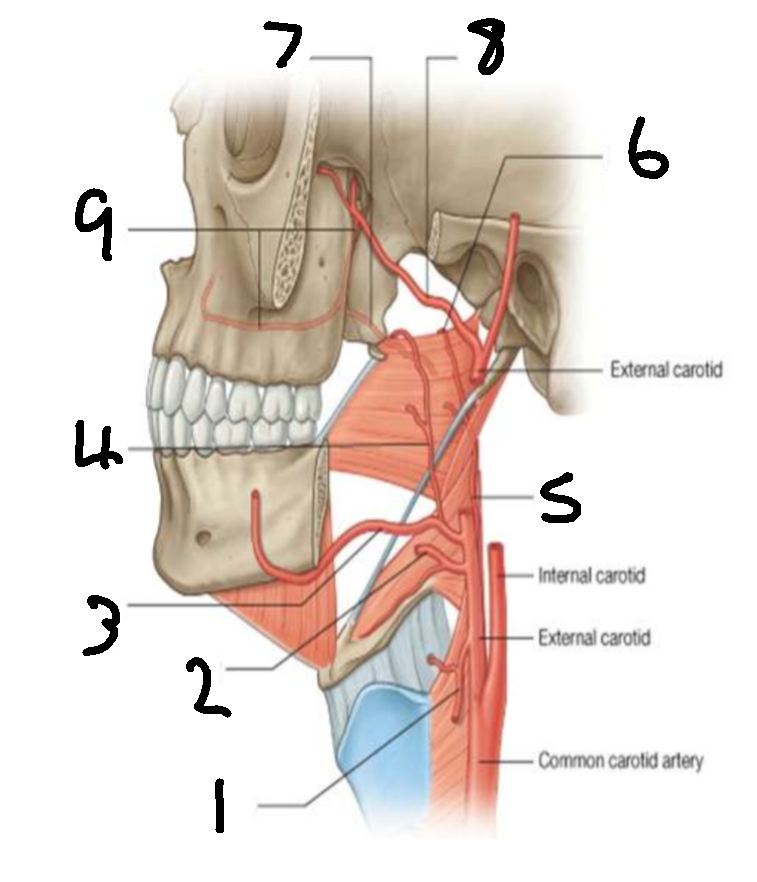

What is 1?

superior thyroid artery

What is 2?

lingual artery

What is 3?

facial artery

What is 4?

ascending palatine artery

What is 5?

ascending pharyngeal artery

What is 6?

palatine branch of pharyngeal artery

What is 7?

lesser palatine artery

What is 8?

maxillary artery

What is 9?

greater palatine artery